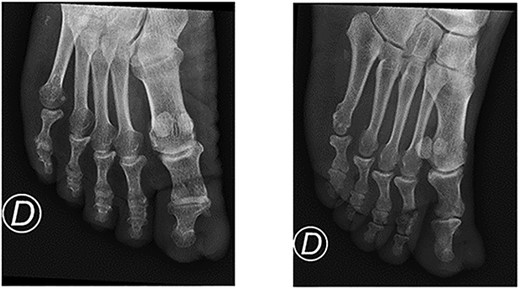

A 64-year-old sub-Saharan African male with diabetes with a long-standing history of a recurring slow-growing periungual mass of the left great toe after multiple surgical wedge excisions for an ingrown toenail presented to the emergency department with acute pain, bleeding and local swelling of the lesion. Physical examination revealed a painful periungual mass (Fig. 1). The toe’s range of motion was conserved and there was no sign of ischemia. An X-ray was performed and did not reveal any bone erosion or osteolytic lesions (Fig. 2). Neither computer tomography (CT) scanning nor magnetic resonance imaging (MRI) were performed. The emergency doctor initially treated the lesion with silver nitrate treatment, and the patient was referred for an orthopaedic consultation for treatment of a recurrent ingrown toenail.

The wound was left open for secondary healing and the patient received careful wound care. At the 6-month follow-up, the patient did not complain of any aesthetic or functional issues or pain and there was no evidence of local recurrence (Figs 7 and 8).

Bone involvement (bone erosion or osteolytic lesions) can be present in one-third of cases [7]. In our case, standard X-ray did not reveal any bone involvement. We did not perform a CT scan or MRI before surgical resection since it would have led to a delayed diagnosis and extra cost. Nevertheless, in unclear cases, MRIs can prove useful. Moreover, a CT scan can detect soft-tissue calcifications and bone erosions [9]. High-resolution ultrasonography (US) with Doppler is readily accessible and cost-effective and can detect small benign tumours and tumour-like conditions of the nail apparatus. However, the quality of the US examination remains operator dependent [9].